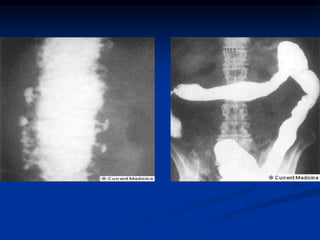

Radiologic features of CD and UC

UC

CD

Feature

Collar button

ulcers

Nodularity

granularity

cobble stoning

string sign of SB